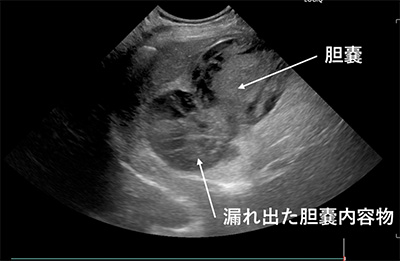

超音波画像診断装置を用いて、心臓および腹部臓器の症例の検査を行います。超音波を使用した検査なので身体への負担を軽減することができる検査方法です。